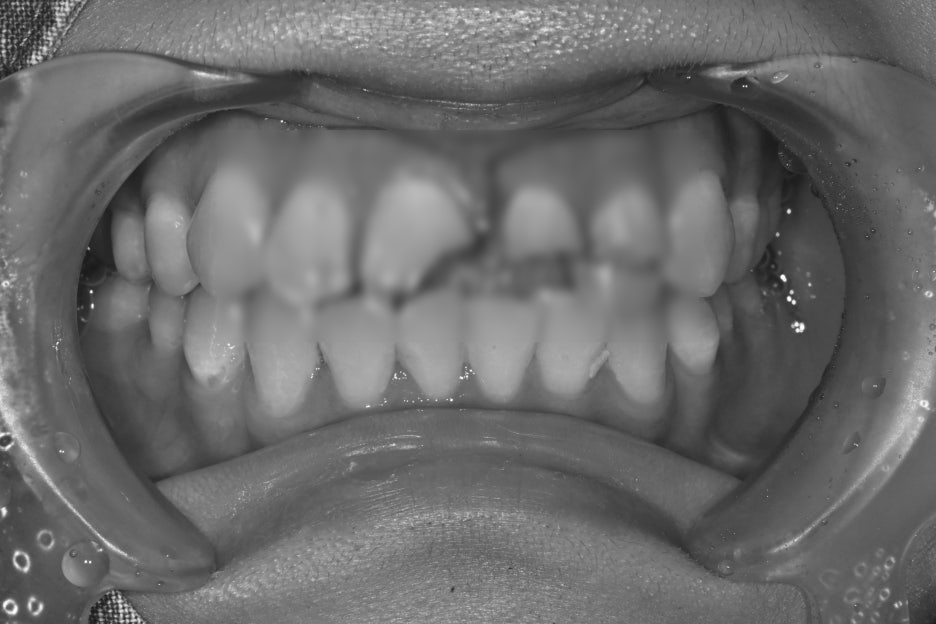

치료 전 후 사진

치료전, 치료후 사진

치료 후 환자분은

“앞니가 다시 가지런해져서 웃을 때

자신감이 생겼다”

며 만족감을 표현하셨습니다.

또한 주변 지인들이 자연스럽다고 말해주어

더욱 안심하셨습니다.